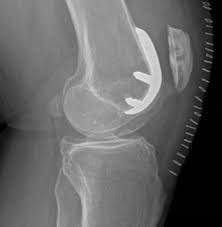

La causa più comune di dolore cronico al ginocchio e di riduzione della sua funzionalità è l'artrosi. Anche se ci sono molti tipi di artrosi, quelli che più comunemente causano dolore al ginocchio sono: l’artrosi cronica senile, l'artrosi secondaria ad artrite reumatoide (malattia infiammatoria su base auto-immune), l'artrosi post-traumatica (esito di fratture) e l’osteonecrosi (infarto dell’osso).La decisione di sottoporsi ad intervento chirurgico di protesi del ginocchio dovrebbe essere una decisione presa di comune accordo tra voi, la vostra famiglia, il vostro Medico di famiglia, e il Chirurgo ortopedico. Il Medico di famiglia può fare riferimento a un Chirurgo ortopedico per una valutazione approfondita e per determinare se nel vostro caso si possa trarre beneficio da questo tipo di chirurgia.Indicazioni alla Protesi di ginocchioCi sono diversi motivi per cui il Medico può raccomandare un intervento chirurgico di protesi di ginocchio. Le persone che beneficiano di protesi del ginocchio spesso hanno:Dolore al ginocchio grave o rigidità che limita le attività quotidiane, tra cui camminare, salire le scale, ed alzarsi o sedersi sulla sedia.Infiammazione cronica e gonfiore al ginocchio che non migliora con il riposo, il ghiaccio, le infiltrazioni o con i farmaci.Deformità del ginocchio: un ginocchio che è diventato flesso e non si estende più (risultato di una grave artrosi) e/o un ginocchio deformato verso l'interno (varo) o verso l'esterno (valgo) (Fig. 3). In questi casi la chirurgia protesica è in grado di riallineare gli arti.Non esiste un'età assoluta o limitazioni di peso per la chirurgia protesica del ginocchio anche se è bene ricordare che questi impianti non durano in eterno (in media 15 anni) e che il peso eccessivo del vostro corpo può essere la causa di una minore longevità della vostra protesi. Quando una protesi fallisce perché si è usurata, dovrà essere sostituita; questo intervento detto di revisione della protesi di ginocchio è un intervento più complesso e più rischioso rispetto all'intervento di primo impianto.L'indicazione alla chirurgia protesica di ginocchio è basata sul dolore di un paziente e sul suo grado di disabilità, non sull'età. La maggior parte dei pazienti che si sottopongono a protesi totale del ginocchio è di età compresa tra i 50 a gli 80 anni, ma i chirurghi ortopedici valutano i pazienti individualmente. Le protesi di ginocchio sono eseguite con successo a tutte le età, dal giovane adolescente con artrite giovanile al paziente anziano con artrosi degenerativa.Aspettative realisticheNon dovete sottoporvi ad intervento di protesi totale del ginocchio se non avete compreso perfettamente tutte le informazioni relative all'intervento chirurgico e soprattutto ai rischi e le complicanze.Un fattore importante nel decidere se sottoporsi o meno a un intervento chirurgico di protesi del ginocchio è capire cosa questa procedura può e cosa non può fare.Più del 90 % delle persone sottoposte a protesi del ginocchio hanno sperimentato una notevole riduzione del dolore del ginocchio e un significativo miglioramento della capacità di eseguire attività comuni della vita quotidiana. Ma la protesi del ginocchio non vi permetterà di fare di più di quanto facevate prima di iniziare a soffrire di artrosi.Con l'uso e l'attività normale, lo spaziatore di plastica di ogni protesi di ginocchio comincia a usurarsi. L'eccessiva attività o l'essere troppo pesanti può accelerare questa usura e può condurvi troppo presto all'intervento di revisione della vostra protesi perché si è mobilizzata o è diventata dolorosa. Pertanto, la maggior parte dei chirurghi sconsiglia di praticare attività come la corsa, il jogging, saltare, o altri sport ad alto impatto per il resto della vita dopo l'intervento chirurgico.Le attività che potete fare a seguito di intervento di protesi del ginocchio comprendono passeggiate illimitate, nuoto, golf, guida, trekking leggero, bicicletta, ballo liscio e altri sport a basso impatto.Con le appropriate cautele, la protesi del vostro ginocchio può durare per molti anni.Possibili complicanze della chirurgiaIl tasso di complicanze a seguito di protesi totale del ginocchio è basso. Complicazioni gravi, quali l'infezione del ginocchio, si verificano in meno del 2% dei pazienti. Le principali complicazioni mediche, come infarto o ictus si verificano anche meno frequentemente. Le malattie croniche (come il diabete) possono aumentare il rischio di complicanze. Anche se è raro, quando però si verificano, queste complicazioni possono prolungare o limitare il pieno recupero.Parlate a fondo delle vostre preoccupazioni con un Ortopedico della nostra equipe prima dell'intervento.Di seguito sono elencate le possibili complicanze:Infezione. L'infezione può verificarsi nella ferita o attorno alla protesi. Può accadere, durante l'ospedalizzazione oppure dopo, quando si va a casa. Può anche verificarsi dopo anni dall'intervento chirurgico. Infezioni localizzate nella zona della ferita sono generalmente trattate con antibiotici. Infezioni gravi o profonde possono richiedere altri interventi chirurgici fino alla rimozione della protesi. Qualsiasi infezione nel vostro corpo anche distante dal ginocchio, può diffondersi e arrivare fino alla vostra protesi.Coaguli di sangue (trombi). Coaguli di sangue nelle vene delle gambe sono la più comune complicanza della chirurgia protesica del ginocchio. Questi coaguli possono essere pericolosi per la vita se si rompono, si staccano e iniziano a viaggiare verso i polmoni dando origine ad un'embolia polmonare. Il chirurgo ortopedico applicherà un programma di prevenzione, che può includere elevazione periodica delle gambe, esercizi per le gambe precoci per aumentare la circolazione, utilizzo di calze elastiche e farmaci per rendere più fluido il sangue (eparina).Problemi dell'impianto. Anche se i materiali, nonché le tecniche chirurgiche, continuano ad avanzare, le superfici impiantate possono logorare e le componenti della vostra protesi possono allentarsi e mobilizzarsi. Inoltre, anche se in media la flessione di 115 ° del vostro ginocchio è generalmente prevista dopo l'intervento chirurgico, occasionalmente possono svilupparsi aderenze cicatriziali del ginocchio, che limiteranno il movimento, soprattutto in quei pazienti che avevano un movimento molto limitato già prima dell'intervento chirurgico.Dolore continuo. Un piccolo numero di pazienti continuano ad avere dolore dopo una protesi di ginocchio e in alcuni casi il motivo è difficile da individuare. Questa complicanza è rara; la stragrande maggioranza dei pazienti riferisce un'esperienza eccellente soprattutto di sollievo dal dolore a seguito di intervento di protesi del ginocchio.Lesioni neurovascolari. Lesioni ai nervi o ai vasi sanguigni intorno al ginocchio sono una complicanza molto rara ma che può verificarsi durante l'intervento chirurgico.Allergie a componenti metalliche (ignote precedentemente al paziente): gli impianti protesici sono costituiti da leghe di vari elementi metallici. In alcuni rari casi si possono verificare fenomeni di intolleranza nei confronti di certuni di questi elementi che possono provocare estrinsecazioni cliniche a diverse forme di gravità.Preparazione all’intervento chirurgicoValutazione medica (prericovero)Se decidete di sottoporvi a intervento chirurgico di protesi totale del ginocchio, il Chirurgo ortopedico programmerà un esame fisico completo con l’anestesista (visita prericovero) diverse settimane prima dell'operazione. Questo è necessario per assicurarsi che siate abbastanza sani per affrontare l'intervento chirurgico e per completare il processo di recupero. Molti pazienti con patologie croniche, come le malattie cardiache, possono anche necessitare una valutazione di uno specialista, come un cardiologo, prima della chirurgia. Presso il nostro Reparto eseguirete questo prericovero (in regime ambulatoriale) circa 1 mese prima dell'intervento dove farete una visita medica generale per valutare le vostre condizioni e correggere eventuali anomalie che possono aumentare i rischi collegati all'anestesia e all'intervento. Durante il prericovero potranno essere eseguite radiografie necessarie per pianificare l’intervento chirurgico.TestDiversi test, come gli esami del sangue e delle urine, e un elettrocardiogramma, possono essere necessari per aiutare il Chirurgo ortopedico nel pianificare il vostro intervento chirurgico.FarmaciInformi il Chirurgo ortopedico e l’anestesista durante il prericovero circa i farmaci che sta assumendo. Vi diranno di quali farmaci dovrete interrompere l'assunzione e quali dovrete continuare a prendere prima dell'intervento chirurgico.Valutazione dei dentiSebbene l'incidenza d’infezione dopo la protesi del ginocchio è molto bassa, questa si può verificare se i batteri entrano nel flusso sanguigno. Per ridurre il rischio d’infezione, le principali procedure dentali (come estrazioni dentarie e lavoro periodontale) devono essere completate prima del vostro intervento chirurgico di protesi totale del ginocchio. Informate il vostro Chirurgo se avete ascessi cronici dentali.Esami delle urineLe persone con una storia recente o di frequenti infezioni urinarie dovrebbero eseguire una valutazione urologica prima dell'intervento chirurgico. Gli uomini più anziani con malattia della prostata dovrebbero completare il trattamento richiesto per il loro problema urologico prima di intraprendere la chirurgia di protesi del ginocchio.Pianificazione socialeAnche per i pazienti sono in grado di camminare con le stampelle o un deambulatore subito dopo l'intervento chirurgico, c’è bisogno di aiuto per diverse settimane per eseguire attività come cucinare, fare il bagno, fare il bucato etc.Presso il nostro ospedale siamo in grado di seguirvi nel vostro recupero per 10 giorni circa dopo l'intervento chirurgico nel nostro reparto di Fisioterapia solo in caso di interventi particolarmente complessi come revisioni protesiche. In alternativa è disponibile un percorso simile fornito totalmente dal Sistema Sanitario Nazionale presso strutture convenzionate. Questo percorso può essere attivato facendone richiesta al momento del ricovero e può aiutarvi quando rientrerete presso la vostra abitazione.L’intervento chirurgicoÈ molto probabile che entrerete in ospedale il giorno prima del vostro intervento.AnestesiaDurante il prericovero sarete valutati da un Medico del team di anestesia. I più comuni tipi di anestesia sono anestesia generale (dormirete) o spinale (sarete svegli, ma il vostro corpo sarà insensibile dalla vita in giù). Il team di anestesia determinerà quale tipo di anestesia sia la più adatta per voi.Intervento chirurgicoUna sostituzione del ginocchio (intervento chiamato anche protesi del ginocchio) potrebbe essere più accuratamente definita come un "rivestimento" del ginocchio perché verrà sostituita solo la superficie delle ossa. Il Chirurgo ortopedico rimuoverà la cartilagine danneggiata e l'osso quindi impianterà il nuovo ginocchio di metallo e plastica per ripristinare l'allineamento e la funzione del vostro ginocchio. La procedura chirurgica richiede in media circa 1-2 ore.La protesi del ginocchio può essere totale o monocompartimentale.Nella protesi totale del ginocchio (Fig. 4 e 5) vengono sostituite con parti metalliche le superfici di cartilagine danneggiate e una piccola quantità di osso sottostante alle estremità del femore e della tibia di tutto il ginocchio. Le parti metalliche generalmente vengono cementate all'osso con uno speciale cemento. Un inserto di plastica speciale molto resistente viene inserito tra le componenti metalliche per creare una superficie di scorrimento liscia. La superficie inferiore della rotula viene tagliata e sostituita con un bottone di plastica che viene anch’esso cementato. Alcuni chirurghi non protesizzano la rotula o lo fanno a seconda del caso, altri (come noi) la protesizzano sempre: non vi è evidenza scientifica in letteratura che dimostri la superiorità di una scelta rispetto all'altra quindi la scelta di protesizzare la rotula o meno dipenderà essenzialmente dall'esperienza del singolo Chirurgo.Presso il nostro reparto vengono utilizzate le tecnologie più innovative di chirurgia computer assistita (5,6) e nuove tecniche chirurgiche (2) che ci consentono di eseguire, quando necessario, interventi chirurgici di protesizzazione in casi complessi con deformità extra-articolari e con tecnica mini-invasiva.Nella protesi monocompartimentale del ginocchio (Fig. 5 e 6) vengono sostituite con parti metalliche le superfici di cartilagine danneggiate e una piccola quantità di osso sottostante alle estremità del femore e della tibia solo di un compartimento (mediale o laterale) del ginocchio. I legamenti del ginocchio non vengono sacrificati. Questa protesi è meno invasiva di quella totale (4), consente un recupero più veloce ma può essere utilizzata solo nei casi in cui l’artrosi non coinvolga gli altri compartimenti del ginocchio (compartimento contro-laterale e/o femoro rotuleo). Esistono anche protesi monocompartimentali di femoro-rotulea: queste vengono utilizzate in casi selezionati di artrosi a carico di questo compartimento.La degenzaÈ molto probabile che resterete in ospedale per diversi (5-7) giorni.Gestione del doloreDopo l'intervento chirurgico, avvertirete dolore, ma il Chirurgo e gli infermieri somministreranno farmaci per ridurlo. La gestione del dolore è una parte importante della vostra guarigione. La deambulazione e il movimento del ginocchio inizierà subito dopo l'intervento chirurgico, appena sentirete meno dolore, questo aiuterà a riprendere le forze in modo più rapido (3).Prevenzione dei coaguli di sangue (Trombosi Venosa Profonda -TVP-)Il chirurgo ortopedico può prescrivere uno o più misure per prevenire i coaguli di sangue e diminuire il gonfiore delle gambe. Questi possono includere calze elastiche vascolari a compressione graduale, e fluidificanti del sangue (eparina).Subito dopo l'intervento chirurgico saranno incoraggiati il movimento del piede e della caviglia per aumentare il flusso di sangue nei muscoli delle gambe e quindi per aiutare a prevenire il gonfiore delle gambe e la formazione di coaguli di sangue.FisioterapiaSarà utilizzata una macchina per il movimento passivo continuo per aiutare a prevenire la rigidità post-operatoria del ginocchio nel primo periodo postoperatorio. Il dispositivo chiamato Kinetec, inoltre, riduce il gonfiore delle gambe, solleva la gamba e migliora la circolazione sanguigna muovendo i muscoli della gamba.La maggior parte dei pazienti inizierà a esercitare il ginocchio il giorno dopo l'intervento. Un fisioterapista vi insegnerà esercizi specifici per rafforzare la gamba e ripristinare il movimento del ginocchio per permettervi di recuperare il prima possibile le normali attività quotidiane subito dopo l'intervento chirurgico.Altre informazioni utiliSi può perdere l'appetito e si può avvertire nausea o stitichezza per un paio di giorni. Queste sono reazioni normali. Può essere necessario che un catetere urinario venga inserito durante l'intervento chirurgico e possono essere necessari emollienti delle feci o lassativi per alleviare la stitichezza causata dai farmaci antidolorifici dopo l'intervento chirurgico.È importante che vi alziate il prima possibile dopo l'intervento chirurgico. Anche a letto, si possono muovere i piedi e le caviglie per pompare regolarmente il sangue nelle gambe. Potrebbe essere necessario indossare calze elastiche vascolari per aiutare il sangue a scorrere nelle gambe.Il vostro soggiorno nel nostro ospedale può durare da 5 a 21 giorni, finché raggiungerete determinate abilità per tornare a casa ed essere sufficientemente autonomi. Se andate subito a casa, avrete comunque bisogno di aiuto in casa per diverse settimane. Potrebbe quindi essere comunque necessario eseguire a domicilio alcuni cicli di riabilitazione.La vostra convalescenza a casaDiverse modifiche possono rendere più facile la deambulazione nella vostra casa durante il recupero. I seguenti suggerimenti possono aiutarvi con le attività quotidiane:Barre di sicurezza o un corrimano sicuro nella vostra doccia o vasca da bagno.Corrimano sicuri lungo le scale.Una sedia stabile con un cuscino del sedile fermo (e una altezza di 45-50 cm).Un rialzo del water se si dispone di un WC basso.Un banco doccia stabile o una sedia per la doccia.Rimozione di tutti i tappeti e degli ostacoli.Uno spazio di vita temporaneo sullo stesso piano, perché fare le scale sarà più difficile durante la prima fase di recupero.Il successo del vostro intervento chirurgico dipenderà in gran parte da come si seguono le istruzioni del vostro Chirurgo ortopedico a casa durante le prime settimane dopo l'intervento chirurgico.La cura della ferita chirurgicaAvrete punti o graffette metalliche che corrono lungo la vostra ferita sulla parte anteriore del ginocchio. I punti o le graffette saranno rimossi circa 3 settimane dopo l'intervento chirurgico.È vietato fare la doccia o il bagno in acqua fino a quando i punti non sono stati rimossi e la ferita non è completamente chiusa ed asciutta. È possibile continuare a bendare la ferita per evitare l'irritazione da indumenti o calze elastiche anche dopo la desutura.Esercizi a casaIl vostro programma di attività dovrebbe includere:Un programma graduale di deambulazione per aumentare lentamente la vostra mobilità, inizialmente in casa e poi fuori.Riprendere le altre attività domestiche normali, come sedersi, alzarsi in piedi, e salire le scale.Esercizi specifici più volte al giorno per ripristinare la circolazione e rafforzare il ginocchio. Probabilmente sarete in grado di eseguire gli esercizi senza aiuto, ma l'aiuto di un fisioterapista in casa o in un centro di riabilitazione le prime settimane dopo l'intervento chirurgico può essere utile.Una cyclette a casa aiuta molto. La cyclette è l'esercizio migliore che potete fare per il vostro ginocchio. Utilizzatela all'inizio con il sellino alto e senza resistenza, con il passare dei giorni abbassate gradualmente il sellino per consentire una maggiore flessione del ginocchio ed aumentate la resistenza del freno per favorire il potenziamento muscolare.Guida della macchinaÈ molto probabile che sarete in grado di riprendere la guida della macchina quando il vostro ginocchio si piegherà sufficientemente da consentirvi di entrare e di sedervi comodamente in auto, e quando il vostro controllo muscolare fornirà il tempo di reazione adeguato per la frenata e l'accelerazione. La maggior parte delle persone riprende la guida dopo circa 4-6 settimane dall'intervento chirurgico.Prevenzione delle complicanze dopo la chirurgiaPrevenzione dei coaguli di sangueSeguite attentamente le istruzioni del vostro Chirurgo ortopedico per ridurre il rischio di coaguli di sangue (trombi) in via di sviluppo durante le prime settimane di recupero. Il chirurgo può raccomandare di continuare ad assumere il farmaco anticoagulante del sangue che è stato iniziato in ospedale (N.B. durante l'assunzione di questi farmaci anticoagulanti bisognerà eseguire le prove ematiche della coagulazione ogni 10-15 giorni per evitare complicanze relative alla loro assunzione). Contattare immediatamente il Medico se si sviluppa uno dei seguenti segnali di pericolo.I segnali di pericolo di coaguli di sangue nella gamba includono:Aumento del dolore al polpaccio.Gonfiore o arrossamento sopra o sotto il ginocchio.Aumentato gonfiore al polpaccio, caviglia e piede.I segnali di pericolo di embolia polmonare (quando un coagulo di sangue è arrivato al polmone) sono:Improvvisa mancanza di respiro.Improvvisa insorgenza di dolore toracico.Dolore toracico localizzato con tosse.Prevenzione delle infezioniUna causa comune d’infezioni a seguito di intervento chirurgico di protesi totale del ginocchio è la presenza di batteri che entrano nel flusso sanguigno durante le procedure dentistiche, infezioni del tratto urinario o infezioni della pelle. Questi batteri possono arrivare intorno al ginocchio e causare un'infezione.Dopo la vostra protesi del ginocchio, è necessario prendere antibiotici preventivi prima di procedure dentali o chirurgiche che potrebbero consentire ai batteri di entrare nel flusso sanguigno.I segnali di pericolo d’infezione. Avvisare immediatamente il Medico se sviluppa uno dei seguenti segni di una possibile infezione della protesi di ginocchio:Febbre persistente (superiore a 38°) per più di 2 giorni.Brividi.Aumento del rossore o gonfiore del ginocchio.Deiscenza, apertura, e fuoriuscita di liquido dalla ferita del ginocchio.Aumento del dolore al ginocchio sia con attività sia a riposo.Evitare le caduteUna caduta durante le prime settimane dopo l'intervento chirurgico può danneggiare il vostro nuovo ginocchio e può comportare la necessità di un ulteriore intervento chirurgico. Le scale sono un pericolo particolare fino a quando il ginocchio non è forte e mobile. Si dovrebbe usare un bastone, stampelle, un girello, corrimani, o avere qualcuno che vi aiuti finché non si è migliorato l'equilibrio, la flessione e la forza.Risultati della Protesi di ginocchioIl vostro nuovo ginocchioUno degli obiettivi della protesi di ginocchio è il miglioramento del movimento, ma il recupero del movimento completo è raro. (1) Il movimento che avrà il vostro ginocchio dopo l'intervento chirurgico può essere previsto in base al movimento che avevate prima dell'intervento chirurgico. La maggior parte dei pazienti può aspettarsi di essere in grado di raddrizzare quasi completamente il ginocchio protesizzato e di piegare il ginocchio a sufficienza per salire le scale ed entrare e uscire da una macchina.La maggior parte delle persone sente un po' di intorpidimento della pelle intorno alla ferita. Si può anche sentire un po' di rigidità, in particolare con l'attività di flessione.La maggior parte delle persone avverte dei click del metallo e plastica quando il ginocchio si piega o quando si cammina. Questo è normale. Queste differenze rispetto ad un ginocchio non protesizzato spesso diminuiscono con il tempo e la maggior parte dei pazienti le trova tollerabili se confrontate con il dolore e le limitazioni funzionali che hanno prima dell'intervento chirurgico.Il vostro nuovo ginocchio può attivare i metal detector necessari per la sicurezza negli aeroporti e in alcuni edifici. Parlate con l'agente di sicurezza della vostra protesi del ginocchio, se si attiva l'allarme.Come proteggere la vostra protesi di ginocchioDopo l'intervento chirurgico, assicuratevi di fare quanto segue:Partecipate a programmi regolari di esercizi leggeri per mantenere la giusta forza e la mobilità del vostro nuovo ginocchio.Prendete precauzioni particolari per evitare cadute e infortuni.Assicuratevi che il vostro dentista sappia che avete una protesi di ginocchio. Dovrete assumere degli antibiotici prima della chirurgia dentale per il resto della vostra vita.Vedete il vostro Chirurgo ortopedico periodicamente per una visita e raggi X, di solito una volta all'anno.La durata della vostra protesi di ginocchioAttualmente, oltre il 90% delle moderne protesi totali di ginocchio sta ancora funzionando bene 15 anni dopo l'intervento chirurgico. Seguire le istruzioni del vostro Chirurgo ortopedico dopo l'intervento e avere cura di proteggere la protesi del ginocchio e la vostra salute generale sono importanti metodi per contribuire al successo finale del vostro intervento.Bibliografia1. Zaffagnini S, Bignozzi S, Saffarini M, Colle F, Sharma B, Kinov PS, Marcacci M, Dejour D. Comparison of stability and kinematics of the natural knee versus a PS TKA with a 'third condyle'. Knee Surg Sports Traumatol Arthrosc. 2014 Aug;22(8):1778-85.2. Iacono F, Raspugli GF, Bruni D, Filardo G, Zaffagnini S, Luetzow WF, Lo Presti M, Akkawi I, Marcheggiani Muccioli GM, Marcacci M. The adductor tubercle as an important landmark to determine the joint line level in total knee arthroplasty: from radiographs to surgical theatre. Knee Surg Sports Traumatol Arthrosc. 2014 Dec;22(12):3034-8.3. Zaffagnini S. Gabapentin did not reduce morphine consumption, pain, or opioid-related side effects in total knee arthroplasty. J Bone Joint Surg Am. 2013 Nov 20;95(22):2060.4. Bruni D, Iacono F, Russo A, Zaffagnini S, Marcheggiani Muccioli GM, Bignozzi S, Bragonzoni L, Marcacci M. Minimally invasive unicompartmental knee replacement: retrospective clinical and radiographic evaluation of 83 patients. Knee Surg Sports Traumatol Arthrosc. 2010 Jun;18(6):710-75. Casino D, Zaffagnini S, Martelli S, Lopomo N, Bignozzi S, Iacono F, Russo A, Marcacci M. Intraoperative evaluation of total knee replacement: kinematic assessment with a navigation system. Knee Surg Sports Traumatol Arthrosc. 2009 Apr;17(4):369-736. Martelli S, Ellis RE, Marcacci M, Zaffagnini S. Total knee arthroplasty kinematics. Computer simulation and intraoperative evaluation. J Arthroplasty. 1998 Feb;13(2):145-55.Autori: Prof. Stefano Zaffagnini, Dr. Giulio Maria Marcheggiani Muccioli, Dr.ssa Maria Pia Neri, Dr. Mirco Lo Presti, Dr. Alessandro Russo, Dr. Alessandro Di Martino, Dr. Alberto Grassi, Dr. Matteo Romagnoli, Dr. Massimiliano Mosca, Prof. Vittorio Vaccari, Struttura Complessa Clinica Ortopedica e Traumatologica II, Istituto Ortopedico Rizzoli.Scheda informativa revisionata il: 7 Giugno 2017.